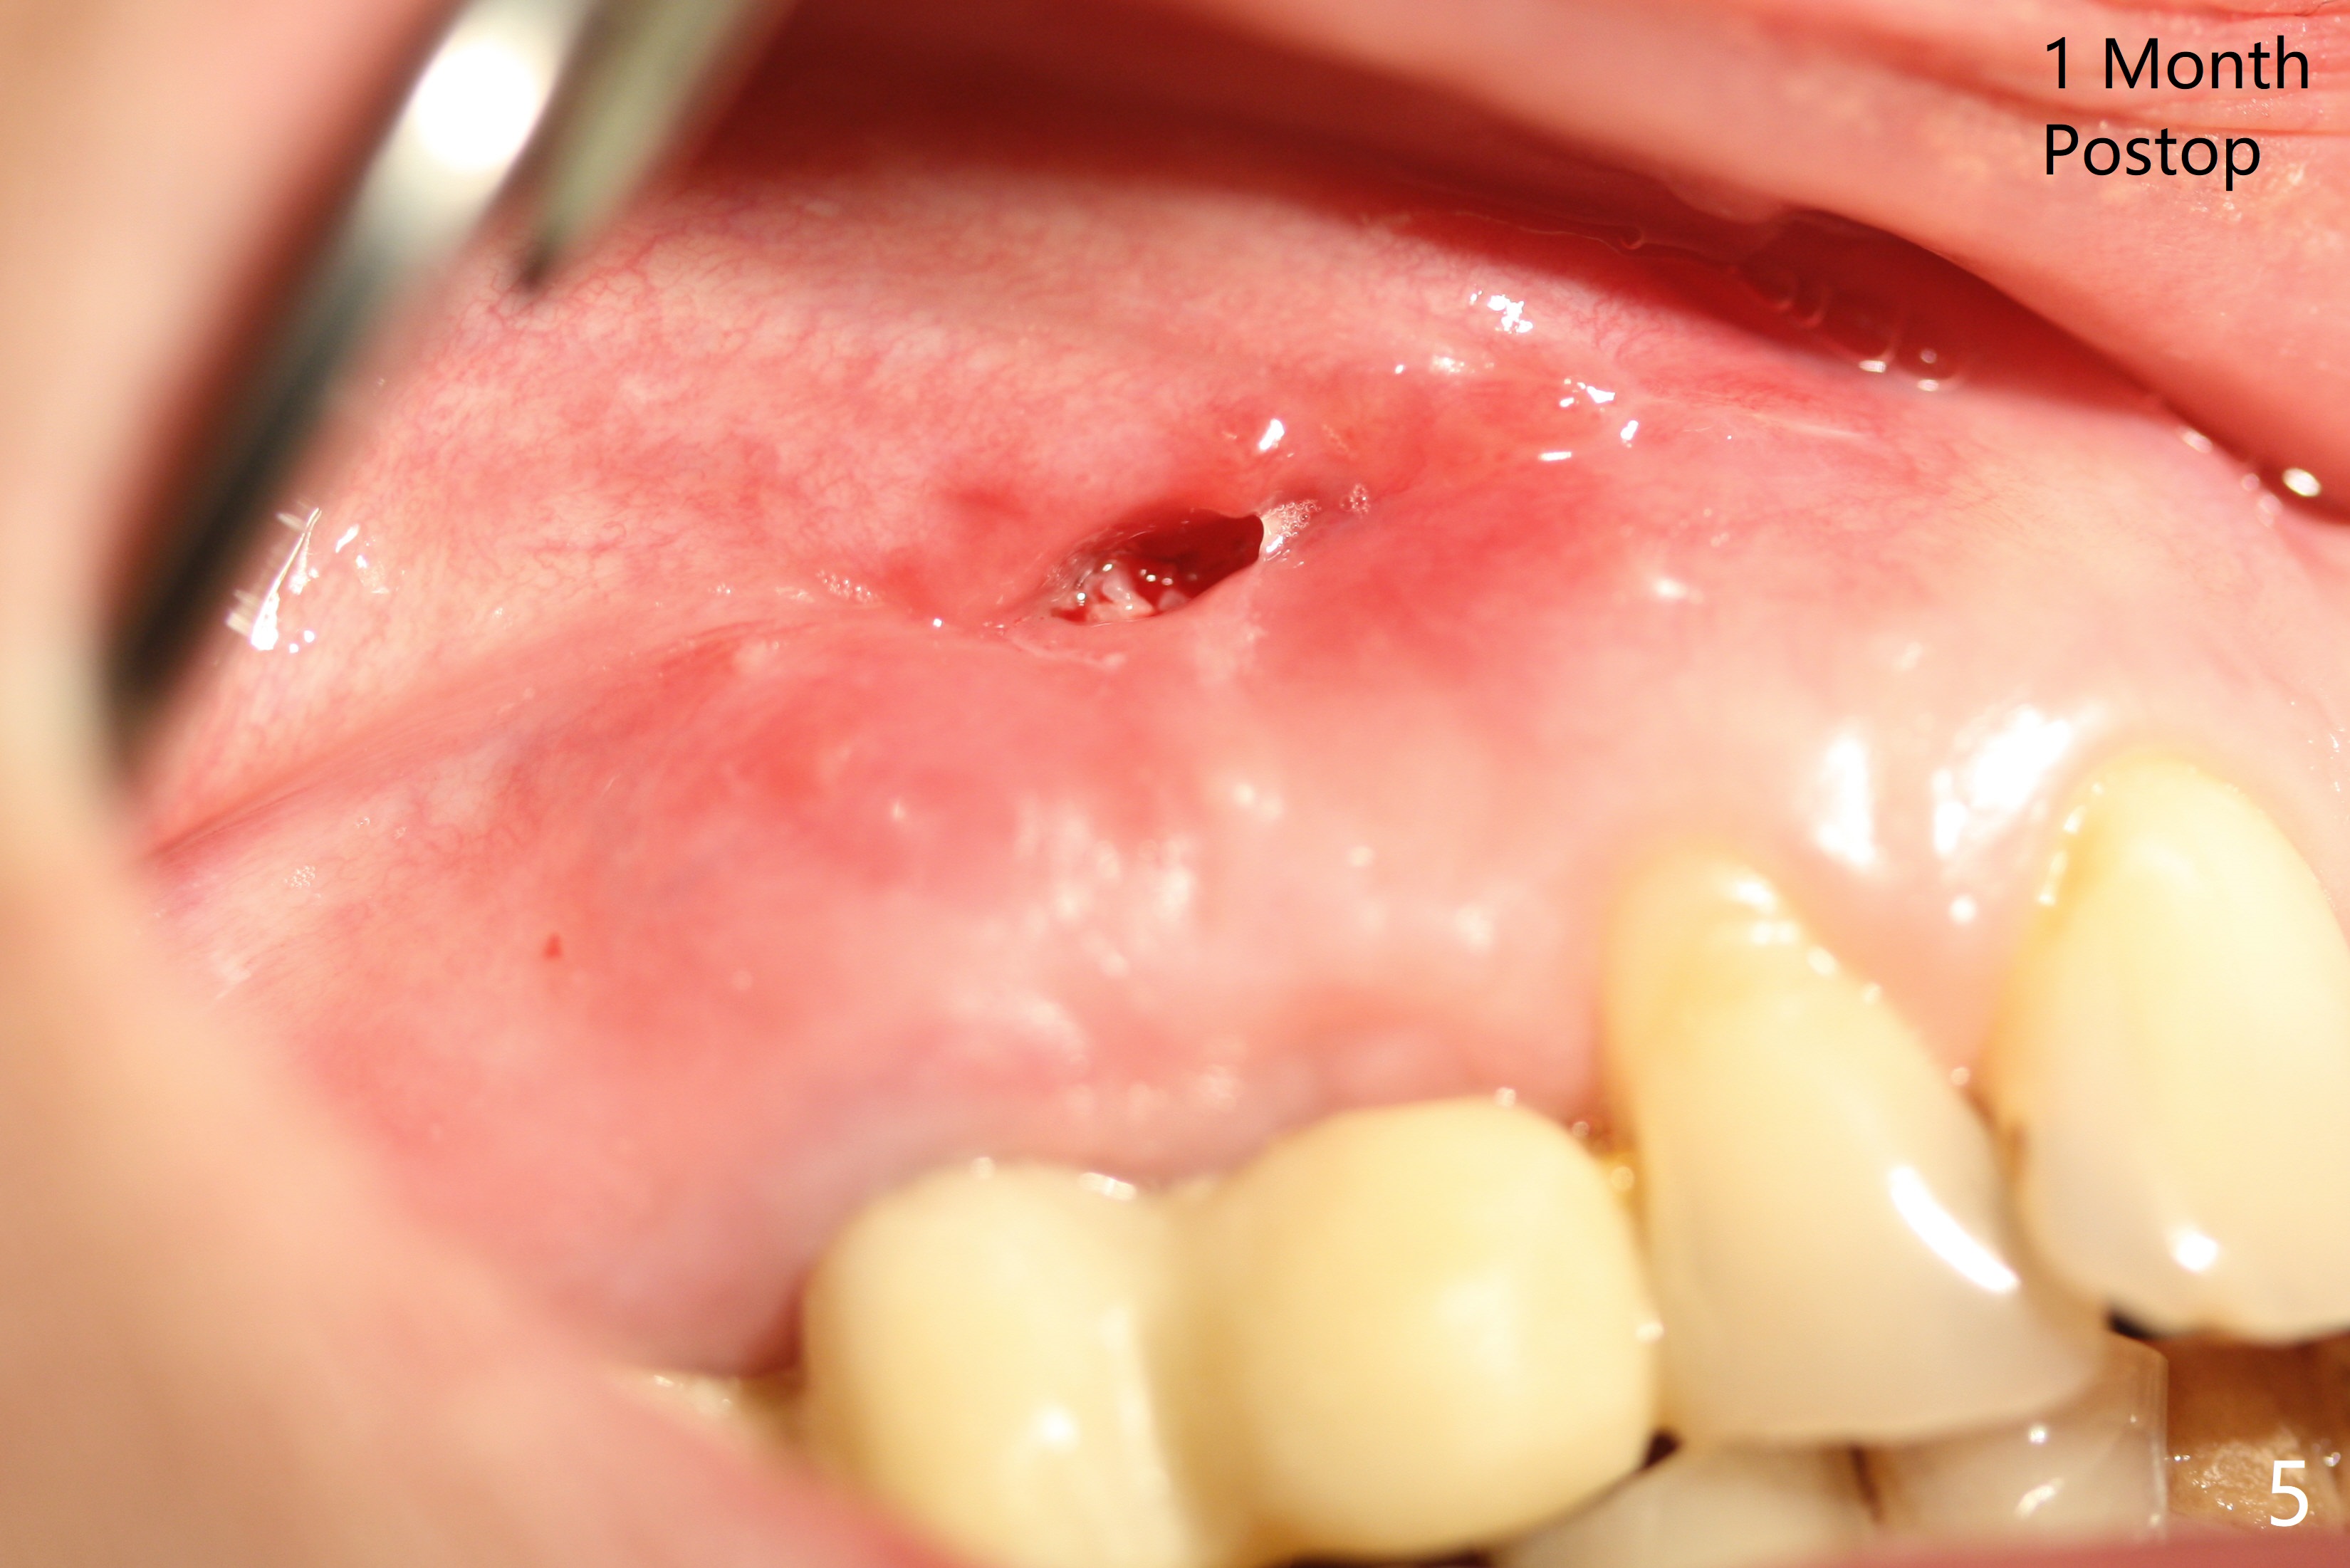

Osteotomy starts with guide and 2.2 mm drill for initial 3.5 mm palatal. A semilunar incision is made buccal to remove the impacted canine (#6 by sectioning). With direct vision buccal and palatal, the final osteotomy is finished free hand with 1.2 and 1.5 mm drills. Initially buccal perforation occurs, the osteotomy route is corrected later (Fig.1). When a 2.5x15 mm 1-piece implant is being placed, it perforates into the buccal concavity again. After redirection, the trajectory seems to be acceptable (Fig.2: CT coronal section). Three coronal implant threads are exposed partially palatal (Fig.3: CT 3-D palatal view). The implant is then turned 2-3 times with insertion torque reaching 40 Ncm. The incision is closed with suture following Osteogen plug placed in the most coronal portion of the socket (Fig.4 P) and allograft (*) in the remaining socket around the apical portion of the implant as well as palatal. The incision does not heal 1 month postop (Fig.5). PRF membrane will be placed next visit. Next visit the wound in fact is healing (Fig.6). PRF is unnecessary. The patient will return for impression 3 months postop. To be cosmetically pleasing, prepare local anesthetic and Laser for gingivectomy (Fig.7 red curved line). There is no bone loss around the implant 3.5 months postop (Fig.8). With topical, minor gingivectomy with laser creates papillae mesial and distal to the implant (Fig.9, 10 (incisal view)). After reline, there is appearance of a canine (Fig.11). The patient returns for impression 5 months postop; there is bone around the apex of the implant (Fig.12 *). The hard and soft tissues remain healthy when final restoration is delivered (Fig.13,14). The buccal plate reforms and #6 socket heals 12 months postop (6 months post cementation, Fig.15). The gingiva remains healthy at #4-6 nearly 2 years post cementation (Fig.16).